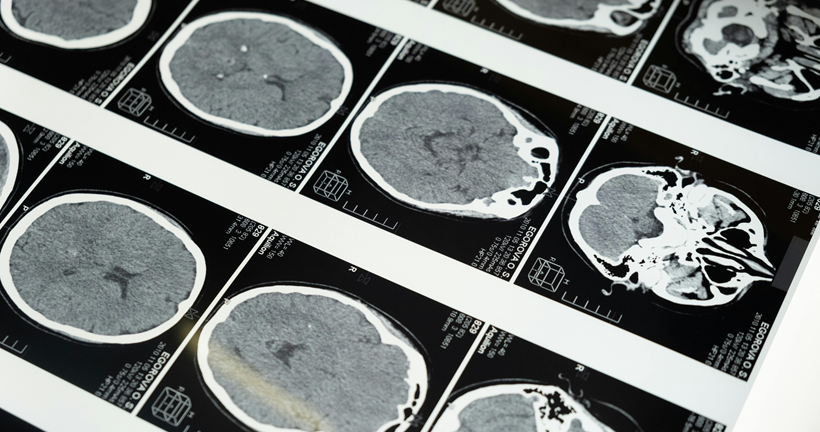

La enfermedad de Alzheimer es la causa más frecuente de demencia y se caracteriza por la acumulación progresiva de placas de beta-amiloide en el cerebro, un proceso que puede comenzar hasta 20 años antes de que aparezcan los primeros síntomas. En este contexto, la medicina nuclear ha revolucionado el diagnóstico gracias a técnicas como la tomografía por emisión de positrones (PET) con trazadores específicos, entre ellos el [18F]Florbetaben, que permite visualizar directamente estos depósitos amiloides in vivo.

El estudio analizado compara dos formas de interpretar estas imágenes PET en pacientes con sospecha de Alzheimer: la evaluación visual, basada en la experiencia de especialistas, y un método más objetivo denominado escala Centiloide, que cuantifica la carga de amiloide en una escala estandarizada de 0 a 100. Esta comparación se realizó en una cohorte de 208 pacientes con deterioro cognitivo leve o demencia leve, seguidos clínicamente durante varios años, lo que permitió establecer un diagnóstico final fiable basado en su evolución.

Los resultados muestran que ambos métodos son altamente precisos y presentan una concordancia muy elevada. En el 95% de los casos, la interpretación visual y la cuantificación mediante Centiloides coincidieron entre sí y con el diagnóstico clínico final. La evaluación visual alcanzó una sensibilidad y especificidad cercanas al 97%, lo que confirma que sigue siendo una herramienta muy sólida en la práctica clínica diaria. Por su parte, el análisis cuantitativo mostró una especificidad aún mayor, lo que sugiere que puede ser especialmente útil para confirmar la ausencia de enfermedad.

Uno de los aspectos más relevantes del estudio es el valor pronóstico de la PET amiloide. En pacientes con deterioro cognitivo leve, la presencia de depósitos amiloides se asoció con una alta probabilidad de progresión a demencia en el seguimiento, lo que refuerza la utilidad de esta técnica para identificar fases tempranas de la enfermedad. Esto es especialmente importante en la actualidad, dado el desarrollo de terapias dirigidas contra el amiloide, donde la detección precoz resulta clave.